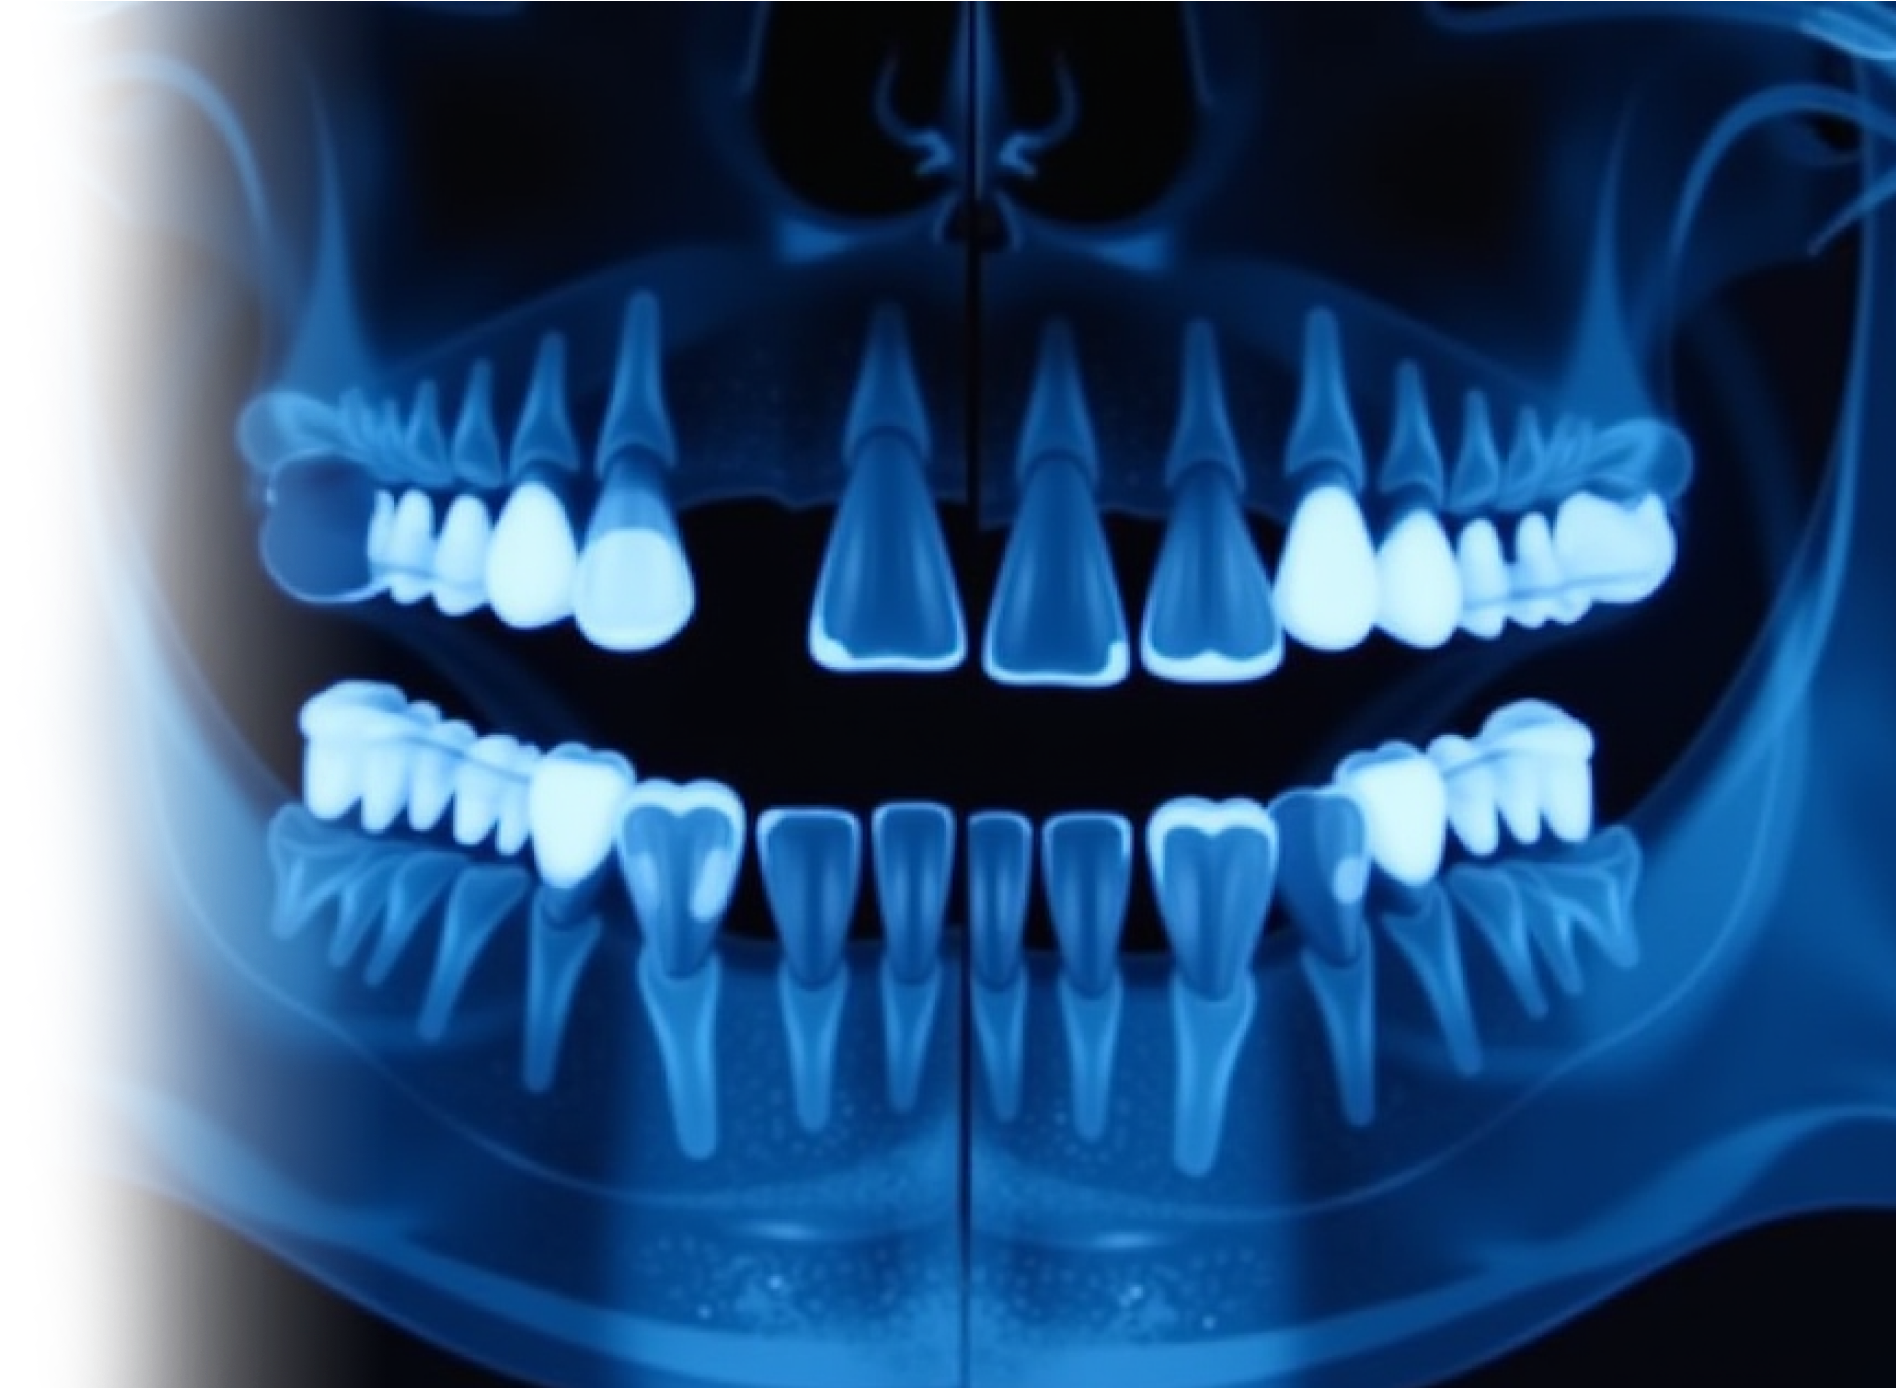

КТ верхней и нижней челюсти

Компьютерная томография челюстей – важный метод прицельного исследования состояния верхней и нижней челюсти.

Для диагностики состояния зубного ряда целесообразно использование КЛКТ.